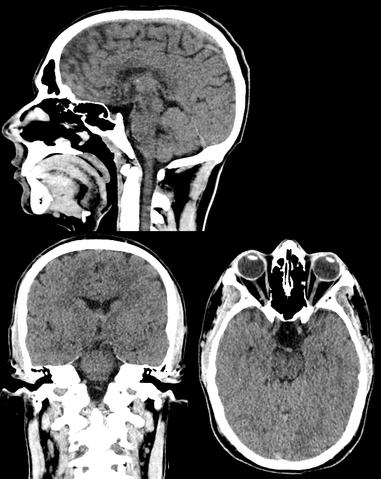

The Computer Tomography (CT) scan represents a widely used and valuable imaging diagnostic tool in modern medicine It enables medical professionals to detect the presence of tumors, traumatic injuries, hemorrhages, and a range of other health abnormalities (Computed Tomography (CT), 2022)

The technique uses a rotating X-ray beam around the patient to generate cross-sectional images, which are then processed and subsequently stacked to create a 3D image However, the procedure requires exposure to ionizing radiation, which poses a potential threat to DNA Ionizing radiation can lead to single-stranded and doublestranded DNA breakages, which may lead to mutations and, ultimately, to cancer. Although the radiation doses used in CT scan procedures are considered generally safe, concerns have been raised regarding children, who are more susceptible to the harmful effects of ionizing radiation, as well as those patients who undergo repeated exposures

Meanwhile, head CT scans, the most commonly performed pediatric CT, posed a higher risk of leukemia and brain cancer, particularly in children under five years old, which had a projected risk of 1 9 cases of leukemia per 10,000 head CT scans The study projected that four million pediatric CT scans of the head, abdomen/pelvis, chest, or spine in the US per year could cause 4,870 future cancers The majority of projected cancers in exposed girls are breast, thyroid, lung cancer, and leukemia, whereas in exposed boys, about half the projected cancers are in the brain, lung, colon cancer, and leukemia Given that effective doses vary between 0.03 – 69.2 mSv, reducing the highest effective doses (25% upper quartile) might aid in potentially preventing over 43% of the projected cancers (Miglioretti et al , 2013) These projections highlight the potential longterm consequences of radiation exposure from CT imaging pediatric patients Healthcare providers should carefully consider the benefits and necessity of these procedures, especially in the pediatric population, which displays the highest vulnerability to the effects of ionizing radiation due to their sensitivity and longer lifespan to develop cancer.

Additionally, Pearce et al. conducted a retrospective cohort study using data from the National Health Services (NHS) Centers in Great Britain between 1985 and 2002, where patients younger than 22 without a previous cancer diagnosis were included Analysis of leukemia and brain tumors involved 178,604 and 176,587 people, respectively Head CT scans constituted the majority of CTs (64%), followed by abdomen/pelvis (9%) and chest CT (7%) The study demonstrated a significant association between radiation doses from CT scans and subsequent incidents of leukemia and brain tumors Patients who received a dose of 30 mGy had a 3 18 times higher risk of developing leukemia compared to those who received doses of less than five mGy

Compared to patients with a dose of less than five mGy, those receiving a dose of 50-74 mGy had a 2 82 times higher risk of developing brain tumors, and those receiving a dose of 50 mGy or more were 3 32 times as likely to develop brain tumors This implies that exposure to 2-3 head CTs, resulting in a cumulative dose of approximately 60 mGy in the brain, increases the risk of developing brain tumors almost

threefold in children below 15 years old. While exposure to 5-10 head CTs can lead to the accumulation of about 50 mGy in red bone marrow dose, tripling the risk of leukemia in children below 15 years of age. In addition, the study also identified statistically significant associations between CT scans and cancer subgroups, including gliomas, schwannomas, meningiomas, acute lymphoblastic leukemia, and myelodysplastic syndromes (Pearce et al , 2012)

https://upload wikimedia org/wikipedia/commo ns/9/96/CT of a normal brain %28thumbnail% 29 png